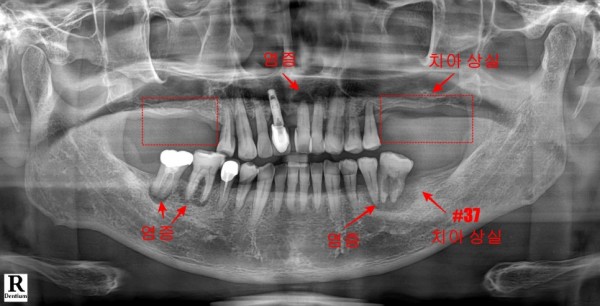

알맞은 진단을 위해 파노라마 촬영과 세밀한 구강 검진을 실시한 결과,

여러 치아에서 심각한 문제들이 발견되었습니다.

앞니 부분과 어금니 부분의 여러 치아에서 치주염이 상당히 진행되어 있었고,

치아 뿌리 끝 부분에도 염증이 광범위하게 퍼져 있는 상태였습니다.

더욱 심각한 것은 위쪽 어금니 부분이 이미 상실되어

오랜 기간 저작 기능을 제대로 하지 못하고 계셨다는 점이었습니다.